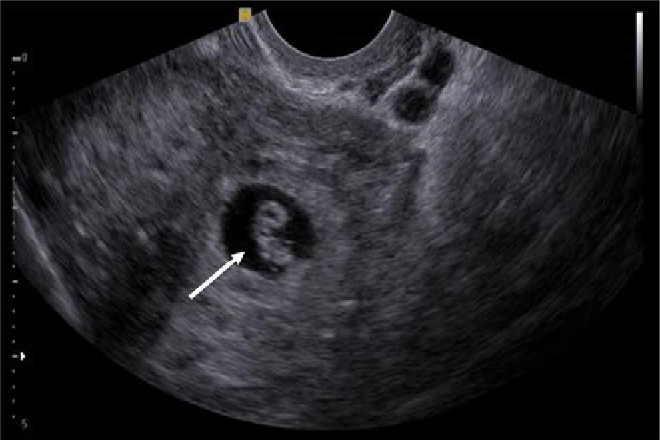

Se sospechó la posibilidad de una complicación obstétrica, usg utero aumentado  de tamaño  con la cavidad vacía. Hacia el cuerno izquierdo del útero, se observó una imagen ecogénica extensa de aproximadamente 10 cm de longitud y contornos irregulares, que parecía corresponder con la solución de continuidad, así como placenta fúndica y posterior, embrión en posición ectópica, de localización abdominal, ubicado hacia epigastrio, transverso, con latidos cardíacos, diámetro biparietal de 76 mm, circunferencia del abdomen de 277 mm, longitud del fémur de 54 mm, para un peso estimado de 1 465 gramos.